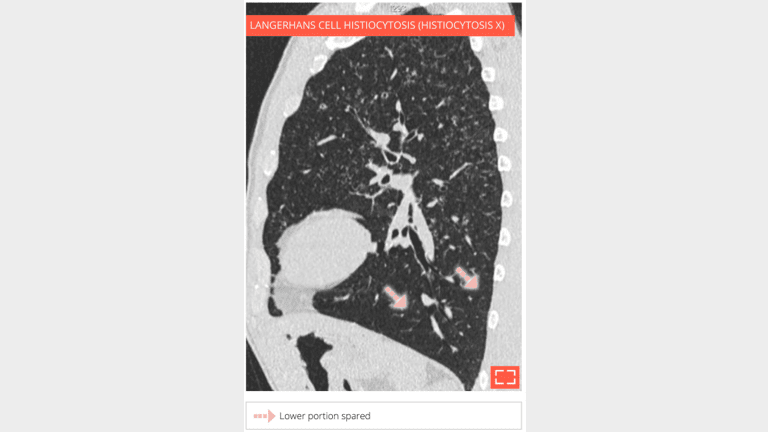

Sagittal reformation in the same patient shows the upper lobe distribution of parenchymal abnormalities

Same patient - coronal reformation shows that the abnormalities are predominating in the upper lungs.